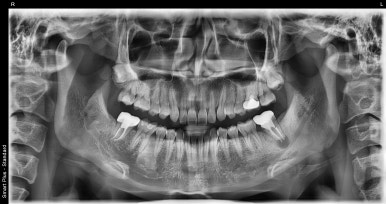

잇몸에혹으로 인해 내원해주신 환자분

치아 뿌리 끝 부분에 염증주머니가 생긴 것을 확인할 수 있습니다.

이런 치아 뿌리 끝 부분의 염증을 전문용어로 ‘치근단 농양’이라고 하는데요.